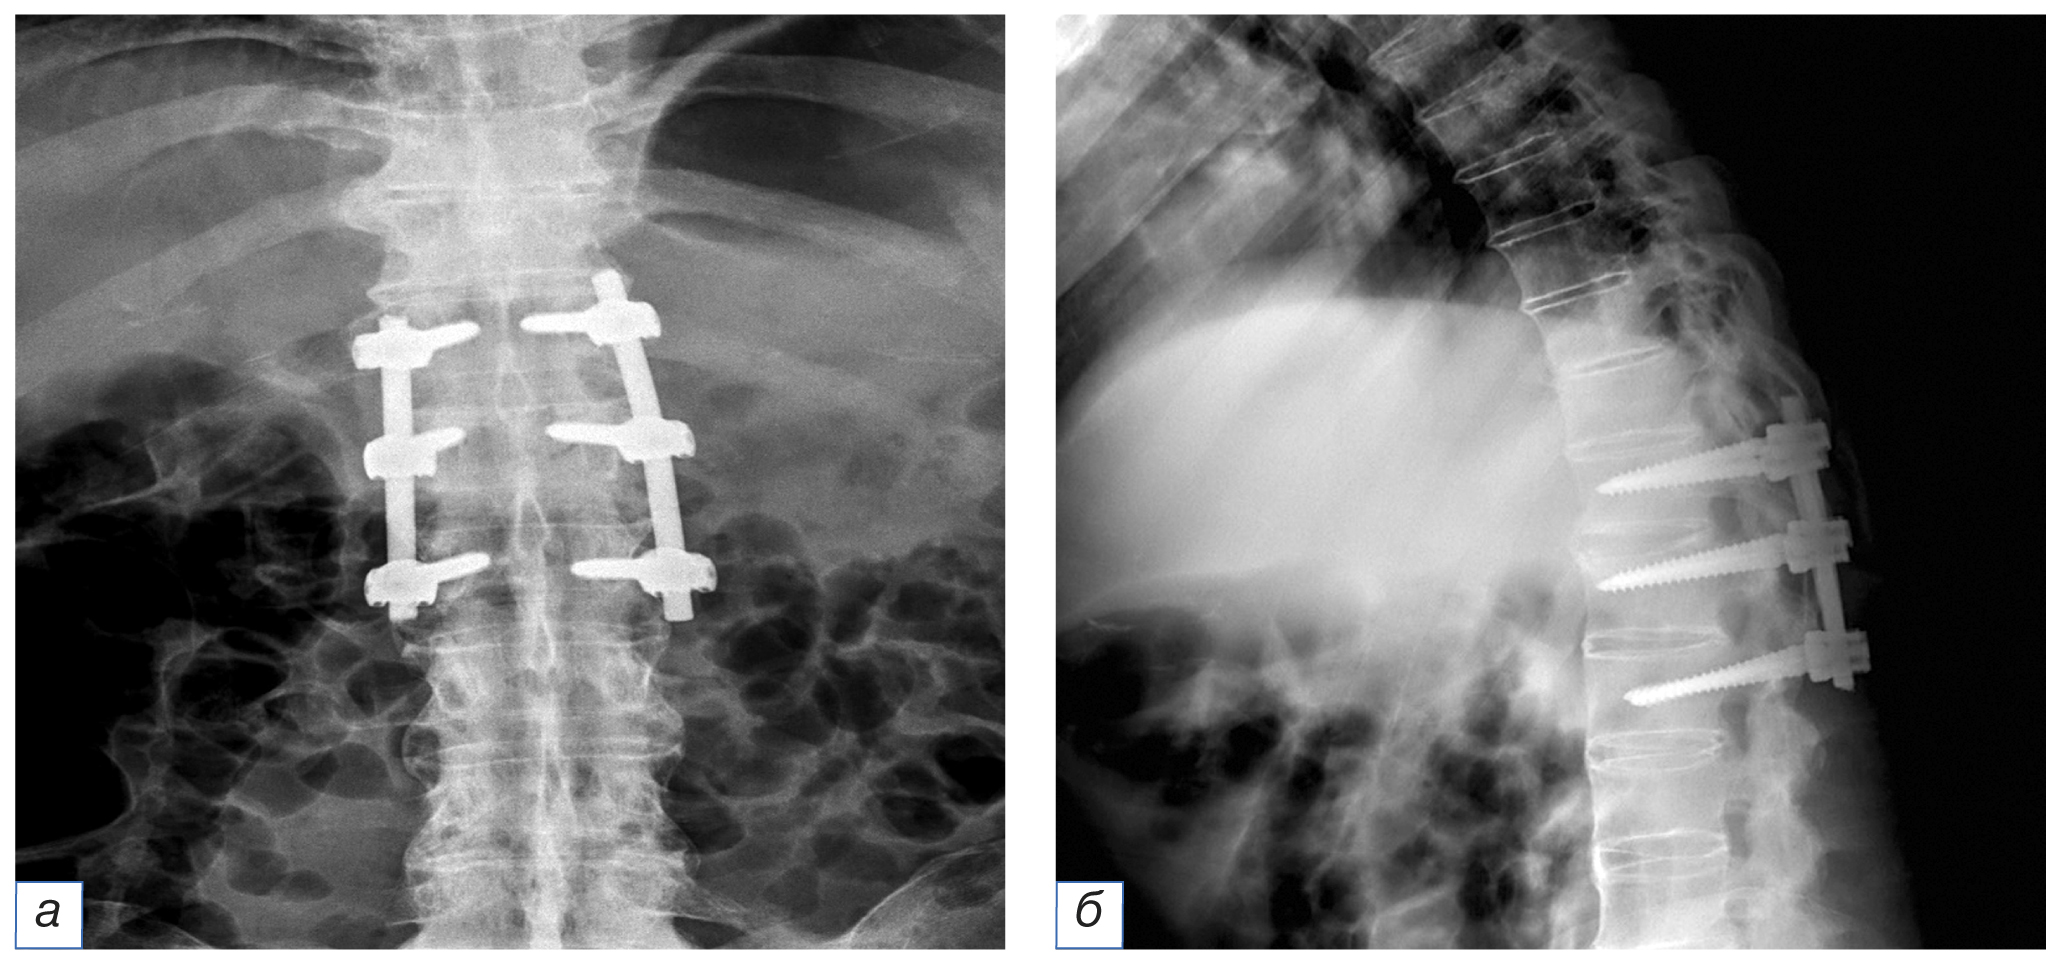

На контрольных рентгенограммах состояние металлоконструкции удовлетворительное (рис. 2).

Рис. 2. Рентгенография грудопоясничного отдела. Транспедикулярная фиксация в тела ThXII, LI, LII позвонков: а — прямая проекция; б — боковая проекция.